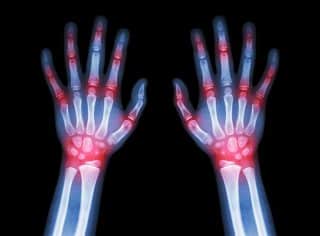

Exploring Treatment Options for Joint Pain: Cortisone Injections, Ultrasound Guidance, and PRP Therapy Read More »